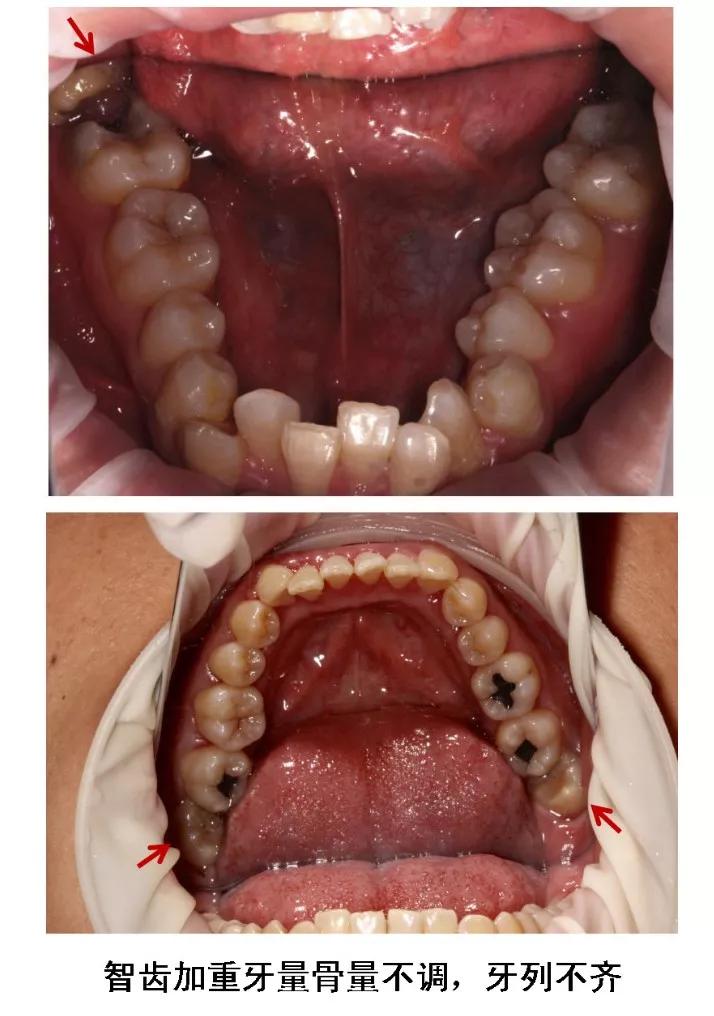

6、牙齿需要矫正,以及在12-16岁做过矫正的小朋友,需要根据正畸医生的建议,及时拔除智齿,以获得完美的牙列和脸型!